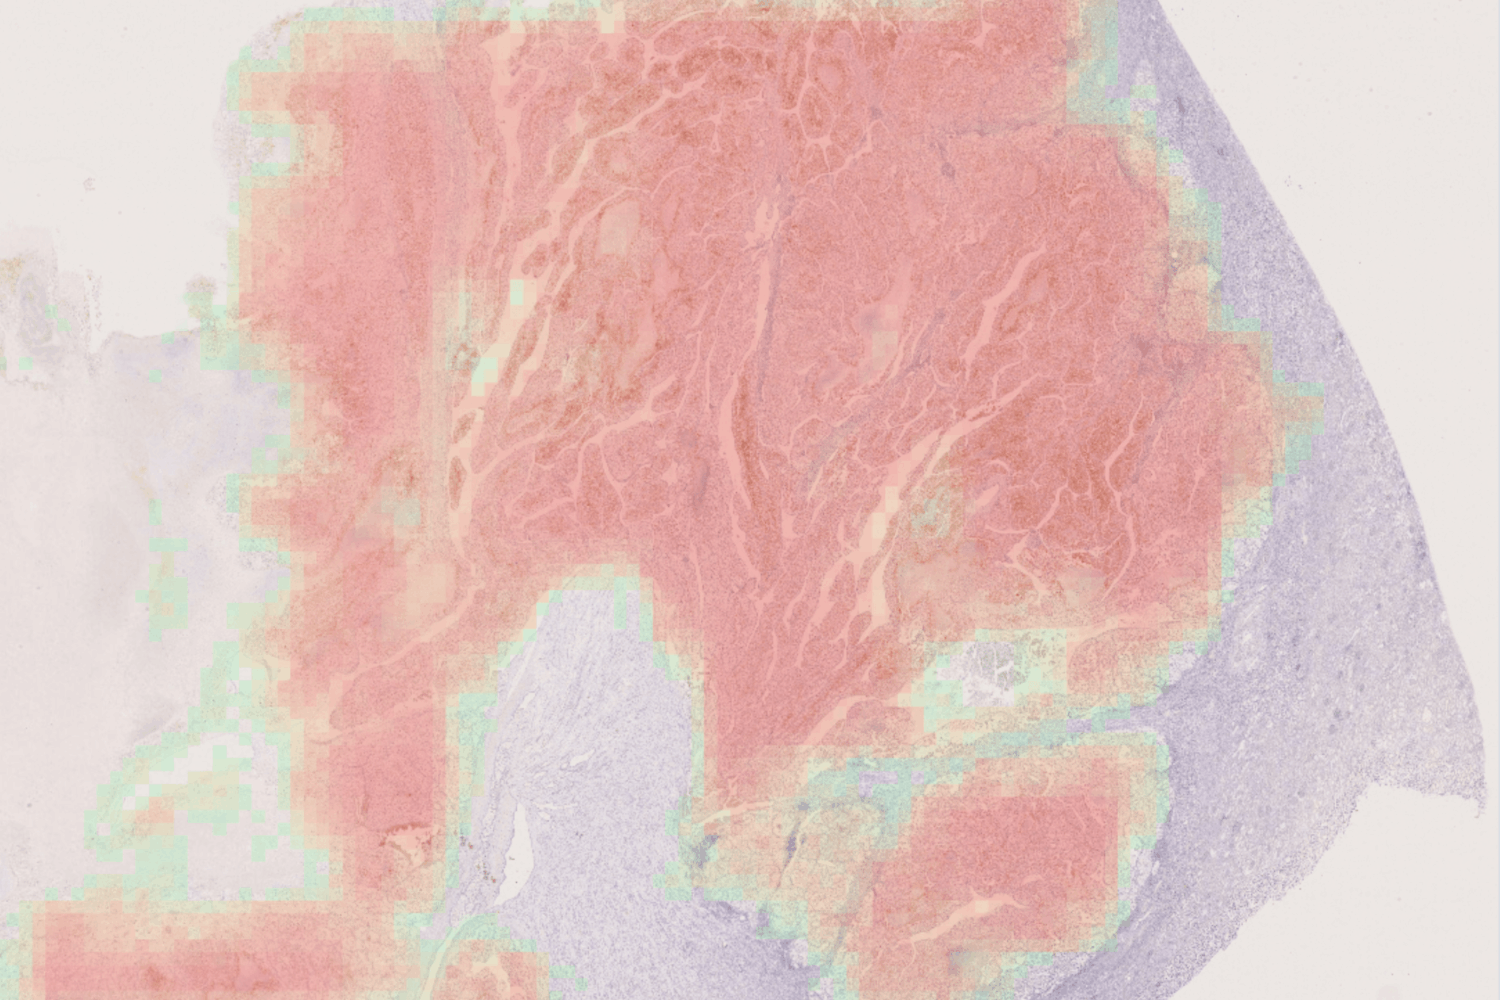

Automatic Detection and Measure of Malignant Lesion in WSI.

SQUAMOUS-CELL CARCINOMA, MELANOMA, BASAL-CELL CARCINOMA